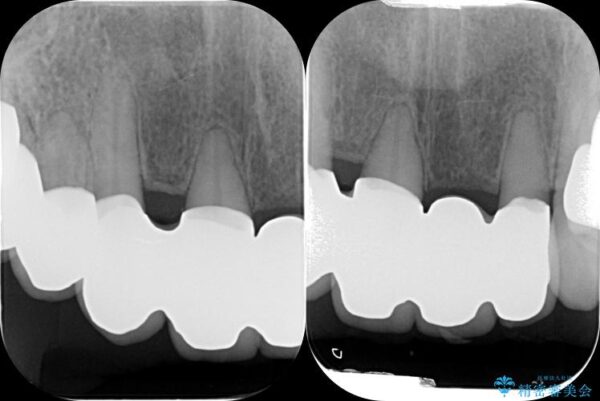

治療中

歯の総合的なマネージメントを行う包括的歯科治療の実践[ 歯周病・矯正・セラミック補綴 ] 治療中画像 歯の総合的なマネージメントを行う包括的歯科治療の実践[ 歯周病・矯正・セラミック補綴 ] 治療中画像 歯の総合的なマネージメントを行う包括的歯科治療の実践[ 歯周病・矯正・セラミック補綴 ] 治療中画像 歯の総合的なマネージメントを行う包括的歯科治療の実践[ 歯周病・矯正・セラミック補綴 ] 治療中画像 歯の総合的なマネージメントを行う包括的歯科治療の実践[ 歯周病・矯正・セラミック補綴 ] 治療中画像 歯の総合的なマネージメントを行う包括的歯科治療の実践[ 歯周病・矯正・セラミック補綴 ] 治療中画像 歯の総合的なマネージメントを行う包括的歯科治療の実践[ 歯周病・矯正・セラミック補綴 ] 治療中画像 歯の総合的なマネージメントを行う包括的歯科治療の実践[ 歯周病・矯正・セラミック補綴 ] 治療中画像 歯の総合的なマネージメントを行う包括的歯科治療の実践[ 歯周病・矯正・セラミック補綴 ] 治療中画像 歯の総合的なマネージメントを行う包括的歯科治療の実践[ 歯周病・矯正・セラミック補綴 ] 治療中画像 歯の総合的なマネージメントを行う包括的歯科治療の実践[ 歯周病・矯正・セラミック補綴 ] 治療中画像